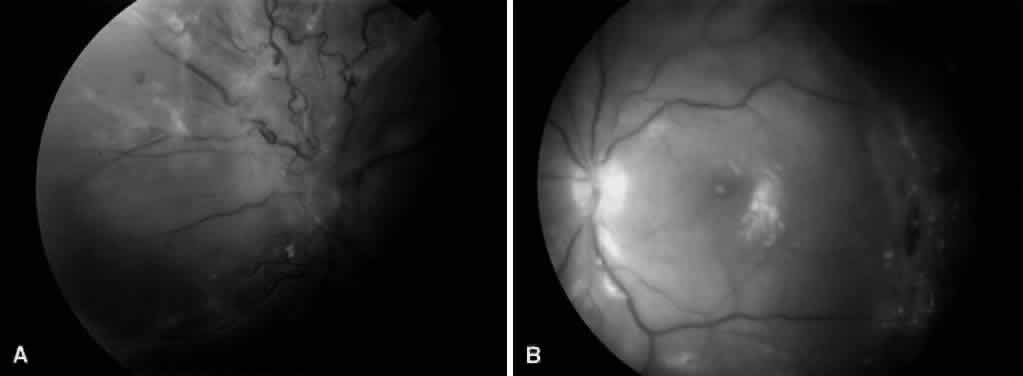

SILICONE OIL IN DIABETIC VITRECTOMY

Another controversial topic is the role of silicone oil in patients with diabetic retinopathy. Whereas some authors58,59 advocate using silicone oil in patients with severe PDR to promote stabilization or regression of iris neovascularization, others60 question its benefit in diabetic patients. Lean and associates were the first to use silicone oil with vitrectomy for severe PDR.61 Several others have since published series of patients where silicone oil was used for severe PDR.62–68 Many of these series involved eyes that had failed prior vitrectomy for PDR and had recurrent retinal detachment with proliferative vitreoretinopathy and iris neovascularization (Fig. 7). These eyes have a particularly poor prognosis and often lose all vision and progress to phthisis. For series that included only such eyes, anatomic success (total retinal reattachment) ranged from 30% to 70%, which may be higher than expected without silicone oil. Visual acuity results, however, remained disappointing. In addition, several complications of silicone oil were reported, including cataract formation, keratopathy, glaucoma, and redetachment secondary to reproliferation. Other reports have examined the use of silicone oil for recurrent vitreous hemorrhages after vitrectomy.37,69,70 Gabel and Beck report a series of 135 consecutive cases of pars plana vitrectomy for PDR where balanced salt solution was used in 69 eyes and silicone oil was used in 66 eyes as a vitreous substitute.71 Indications for use of silicone oil included the presence of several retinotomies or retinectomies, or sharply increased risk for rebleeding. Postoperatively, for eyes with a minimum of 6 months' follow-up (only 58 of 135 eyes), the two groups achieved similar functional results, with 18 of 23 eyes (78%) in the silicone oil group and 27 of 35 eyes (77%) in the balanced salt solution group achieving visual acuity greater than or equal to 0.02 (4/200). A worse functional outcome would be expected from the eyes where silicone oil was used because of a worse preoperative condition. Thus, these findings may indicate that silicone oil is useful in such eyes. However, no comparison was made to similar eyes treated with long-acting gas tamponade. Certain characteristics of silicone oil may be advantageous for eyes with PDR. Because of its optical qualities, earlier visual rehabilitation may be possible, and fundus details are clearly visible, permitting intraoperative and postoperative laser photocoagulation. Also, silicone oil, unlike gases, provides indefinite retinal tamponade. Experimental evidence in animal models suggests that silicone oil may inhibit iris neovascularization by compartmentalizing the eye and preventing anterior diffusion of vasoproliferative substances.57,72 However, clinical studies have been unable to confirm this because of the multiple variables that may lead to iris neovascularization. Oil emulsification and reproliferation may be more common in diabetics than in nondiabetic patients. If silicone oil is to be used in an aphakic or pseudophakic eye of a diabetic, it is important to create a large inferior iridectomy to prevent silicone oil from migrating anteriorly and contacting the cornea. Madreperla and McCuen showed that postoperative closure of the iridectomy occurs more frequently in diabetics than in nondiabetics, and closure of the iridectomy is highly correlated with anterior oil migration.73

Fig. 7. A. Preoperative fundus photograph of an eye with recurrent combined retinal detachment from proliferative diabetic retinopathy and proliferative vitreoretinopathy. B. Postoperative fundus photograph of the same eye. The retina has been successfully reattached using silicone oil tamponade.